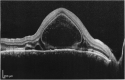

Figures